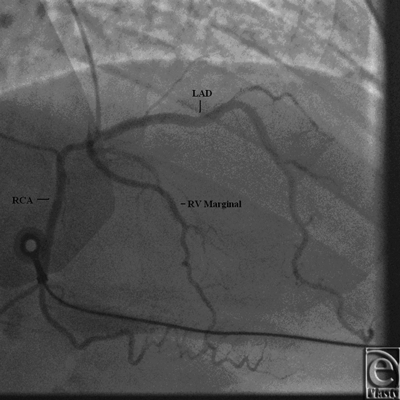

Initial 2D echocardiogram showed severe mitral valve regurgitation with a left ventricular ejection fraction of 35%. Furthermore, the valvular anatomy appeared peculiar; based on right ventricle (RV) and left ventricle morphology, CCTGA was suspected. A transesophageal echocardiography (TEE) was performed for further evaluation. It confirmed our diagnosis of CCTGA. Also, the (TEE) showed a hypertrophied RV and severe systemic AV (SAV) valve regurgitation (Figs 1 and 2). There was no evidence of an atrial septal defect, VSD, or patent ductus arteriosus. An MRI (magnetic resonance imaging) was performed to elucidate the anatomy. It affirmed the diagnosis of CCTGA with a trileaflet SAV that demonstrated severe regurgitation from the systemic ventricle (SV) to left atrium (Figs 3-6). Because of the patient's symptoms and severity of the regurgitation of the SAV, we decided to perform SAV replacement. Preoperative cardiac catheterization showed left dominant coronary circulation with left circumflex and a ramus intermedius originating from left cusp through separate ostia (Figs 7 and 8). Left anterior descending artery originated from proximal right coronary artery through a single ostium from right coronary cusp (Figs 8 and 9). No obstructive coronary heart disease was found and the patient proceeded to surgery.

![]() |

| Figure 7. Coronary angiogram showing origins of left circumflex (LCx) and ramus intermedius from different ostia on left coronary cusp. |

Significant coronary artery anomalies have also been described in literature with CCTGA.5-7 In a study performed by Ismat et al8 with autopsy on pediatric hearts having CCTGA, coronary circulation was shown to be more consistent as compared to other CHD.8-12 Such anomalies should be kept in mind, when performing corrective surgery.13 Coronary circulation can be delineated with the help of coronary angiography or MRI. While coronary angiography has an added benefit in evaluation of coronary circulation and intraluminal abnormalities, an MRI is beneficial for further characterization of anatomical structures and to identify other associated anomalies. In our case, the aberrations were delineated with coronary angiography. The patient had a common origin for the right coronary artery and left anterior descending artery. Meanwhile, the left coronary cusp gave off 2 branches, namely, left circumflex artery and a ramus intermedius through separate ostia. This anomaly has never been described before in literature. Although the coronary anatomy is not directly involved in surgical correction, variants must be kept in mind during manipulation especially when undergoing corrective surgery.